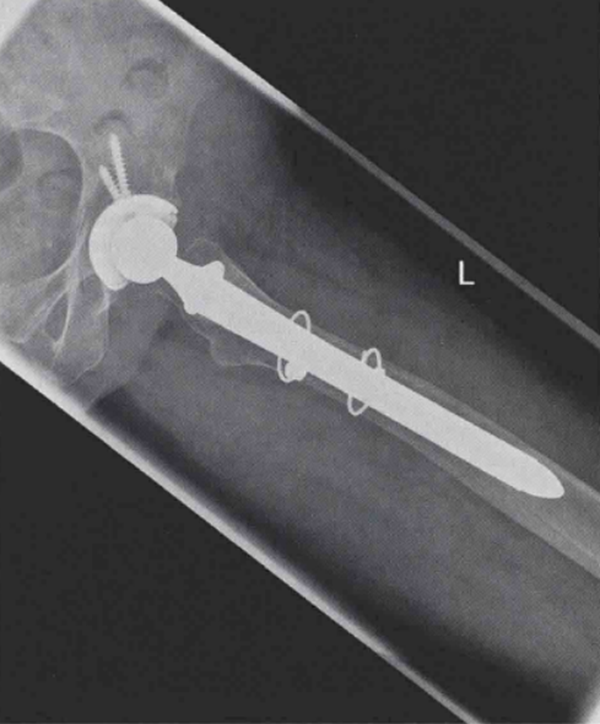

术后,患者可在完全负重下活动。术后X线片显示效果满意(图4和图5)。患者持续恢复良好。3个月随访中,患者完全无不适症状。

图5 左髋翻修术后侧位X线片,使用远端固定型柄跨过骨折端,达到良好的远端固定效果2